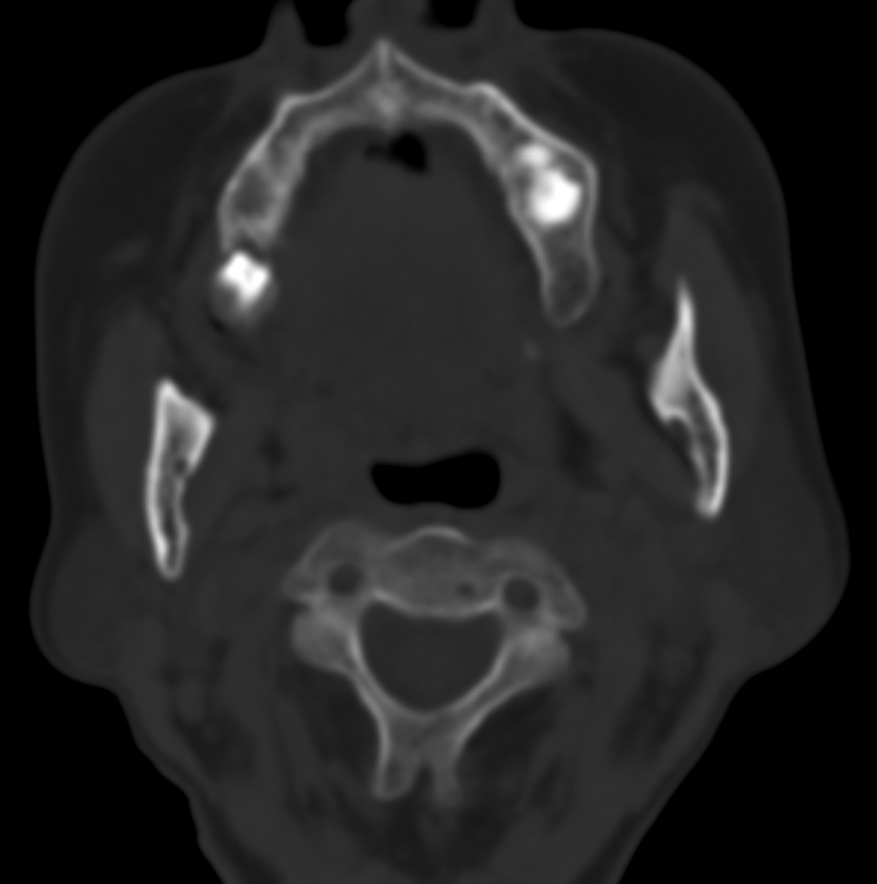

女,68岁。发现上唇无痛性肿块2年多,查体局部皮肤隆起,其余未见异常。

病灶ct值约42hu。

病理结果:唾液腺混合瘤。